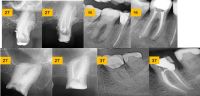

Jednoposjetno endodontsko liječenje...

Voditelj: Prof. dr. sc. Ivica Anić

Datum: 05.04.2025. / Vrsta: radni tečaj / Poziv na broj: 5-16 / Cijena: 230 eur   / Mjesto održavanja: Stomatološki fakultet – predavaonica / pretklinika / HKDM bodovi: 10